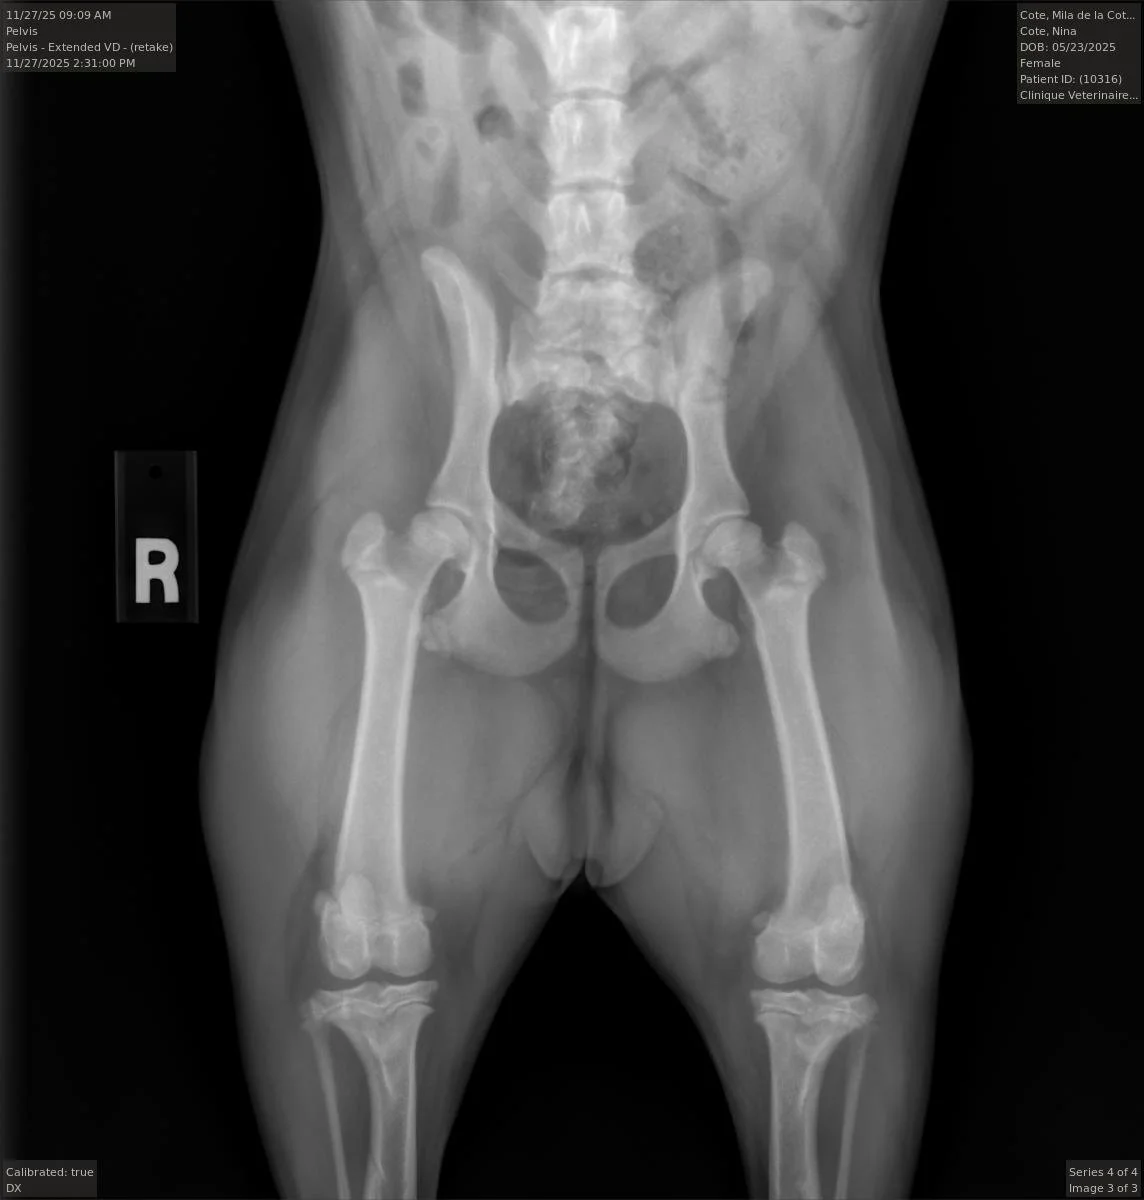

Nous commencerons les tests OFA de la race dès l'âge de 6 mois.

Mila, notre petite progéniture issue de l'union de Hailey de notre programme d'élevage. Son père descend d'une lignée très distinguée, avec d'excellents résultats en ce qui concerne la santé des hanches. Nous sommes impatients de la voir se développer.